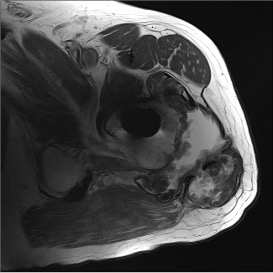

Adverse Local Tissue Reactions (ALTR)

Mechanism

Generation of biologically active, nanometer sized metal particles

- cause large inflammatory reaction

- pseudotumour (AKA aseptic lymphocyte-dominant vasculitis associated lesion ALVAL)

- can cause extensive soft tissue and bone loss

Diagnosis

Pain

High serum ion levels

Loosening on xray

Pseudotumour on MRI

Incidence

- 288 Depuy ASR THA 6 years post surgery

- moderate or severe ATLR in 24% on MRI